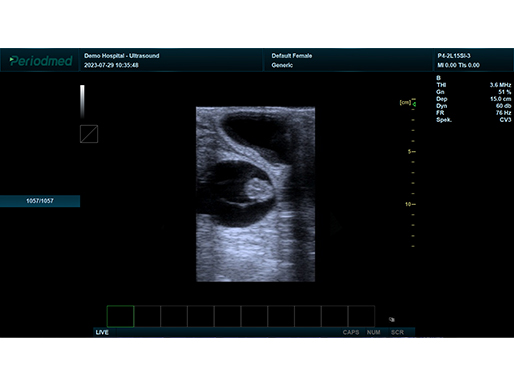

B模式 腹部 羊

B模式 怀孕 牛

凸阵探头-B模式-腹部 羊

凸阵探头-B模式-子宫 海豚

凸阵探头-B模式-子宫 海豚